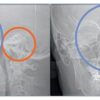

- Đánh giá TMJ: hình ảnh lồi cầu 3D, không gian khớp